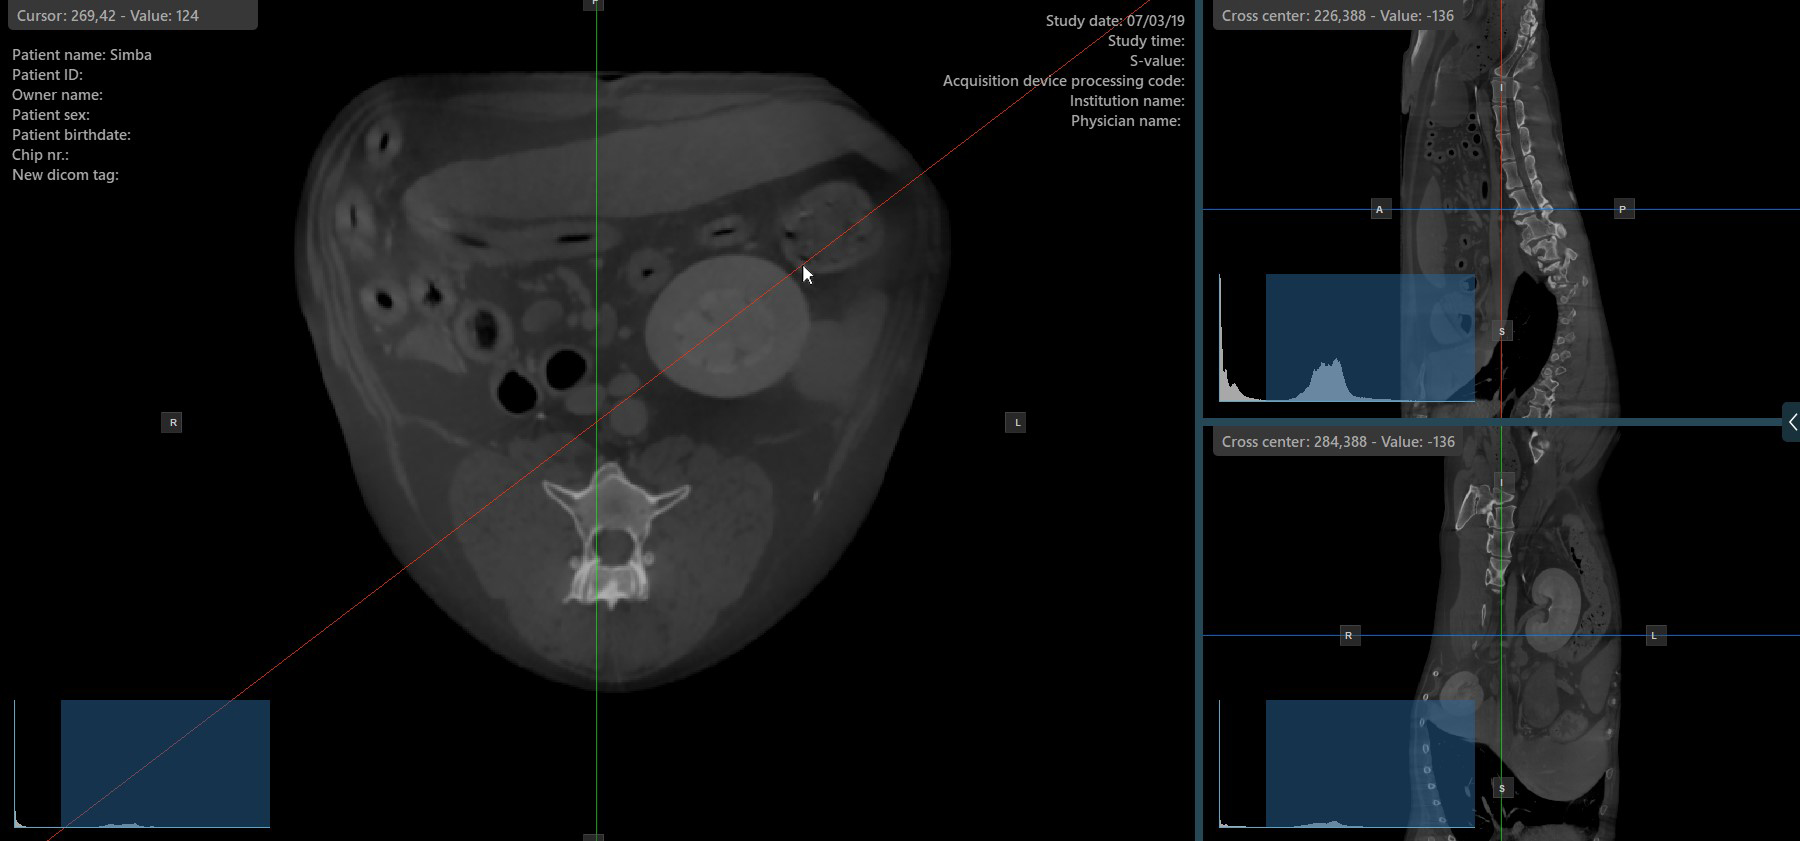

Slicer-Rotation ändern¶

Das Ändern der Rotation eines Slicers verändert die Orientierung der entsprechenden Bildebenen. Einzelne Slicer können mit dem Werkzeug Select Item (Default) ausgewählt werden, das standardmäßig der rechten Maustaste zugewiesen ist.

Sobald der bestimmte Slicer ausgewählt ist, ziehen Sie ihn in die gewünschte Richtung, um ihn zu drehen. Die Orientierung der entsprechenden Bildebene ändert sich entsprechend.